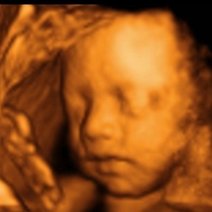

胎儿是可以做亲子鉴定的。通常有采集孕妇静脉血的无创亲子鉴定、绒毛亲子鉴定和羊水亲子鉴定等,可以通过鉴定其中的DNA来判断和确认亲缘关系。 无创亲子鉴定...5683人收听

- 胎儿亲子鉴定有两种方式:绒毛活检和羊水鉴定。怀孕10周以后可以做绒毛穿刺手术检测,怀孕16周以后就可以做羊水检测了。胎儿亲子鉴定,是指利用基因技术鉴定胎儿遗传意义上的父亲。当胎儿遗传意义上的父亲是谁不

- 胎儿胎儿亲子鉴定亲子鉴定胎儿亲子鉴定是指利用基因技术鉴定胎儿遗传意义上的父亲。当胎儿遗传意义上的父亲是谁不得而知时,产前亲子鉴定可从孕妇的羊水中提取细胞,通过鉴定胎儿的脱氧核糖核酸确认父子关系。胎儿亲子鉴定必须提供的样本为胎儿样本羊水、绒毛